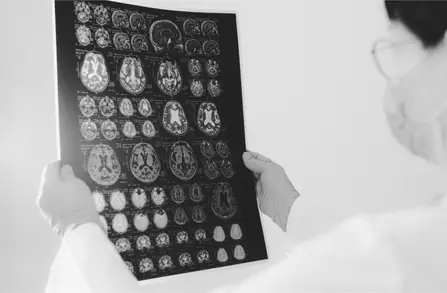

What is a Traumatic Brain Injury (TBI) Case?

Traumatic brain injuries occur when a sudden impact or jolt to the head disrupts the normal functioning of the brain. TBIs can range from mild concussions to severe brain damage, with long-lasting effects on cognitive, physical, and emotional health. Common causes include car accidents, falls, sports injuries, and workplace accidents.

Traumatic Brain Injuries